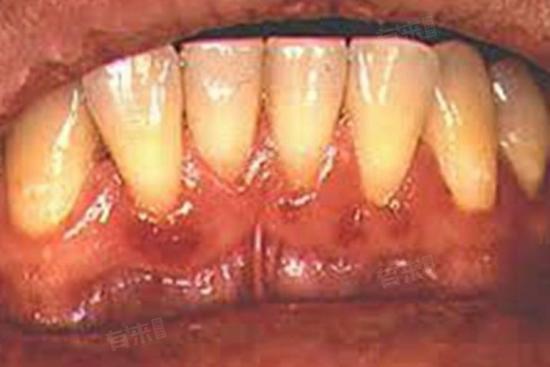

3、牙龈线形红斑:这是艾滋病患者较为常见的口腔症状之一,表现为沿着牙龈边缘出现界限清楚的火红的带状红斑,与一般的牙龈炎不同,它通常没有明显的疼痛和出血症状。这种红斑一般不易消退,常规的口腔治疗对其效果不明显。